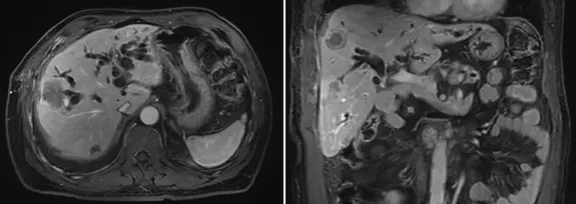

6月復(fù)查,上腹部MRI提示考慮肝內(nèi)多發(fā)轉(zhuǎn)移,行標(biāo)準(zhǔn)治療,予全身化療;

壺腹部腺癌術(shù)后改變,左右肝管匯合部異常信號(hào),不除外復(fù)發(fā)可能;考慮肝內(nèi)多發(fā)轉(zhuǎn)移瘤形成

所見(jiàn)右側(cè)胸腔積液,右下肺片狀異常信號(hào),建議進(jìn)一步胸部檢查

影像學(xué)檢查結(jié)果